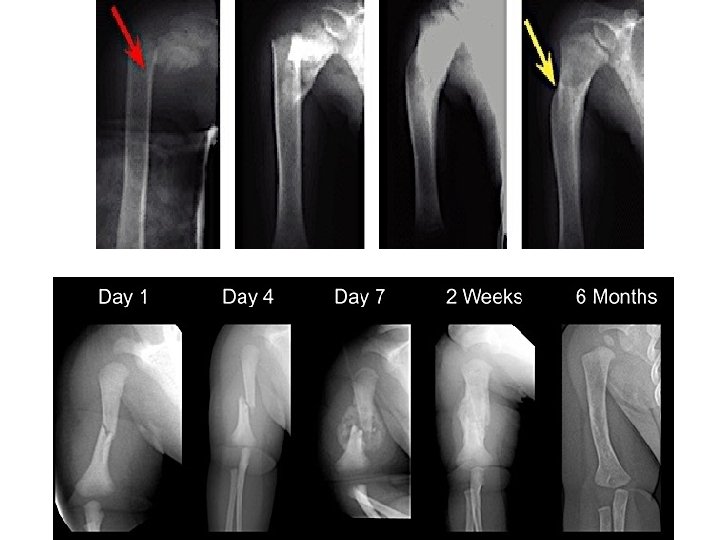

Femoral Shaft Fractures

Femoral Shaft # • 1. 6% of all pediatric # • M>F • Age: – (2 – 4) years old – Mid-adolescence • Adolescence >90% due to RTA

Femoral Shaft #- Mechanism of Injury • Direct trauma: – RTA, – Fall, or – Child abuse • Indirect trauma: – Rotational injury • Pathologic #: – Osteogenesis imperfecta, – Nonossifying fibroma, – Bone cysts, and – Tumors

Femoral Shaft #- Clinical Evaluation • Look: – – – Pain, Swelling of the thigh, Inability to ambulate, and Variable gross deformity Careful O/E of the overlying soft tissues to rule out the possibility of an open fracture (puncture wound) • Feel: – Tender # site • Careful neurovascular examination is essential

Femoral Shaft #- Radiology • AP and lateral views • Must include hip, knee joints

Femoral Shaft #- Classification Descriptive Anatomic • Open or closed • Level of fracture: • • (proximal, middle, distal) ⅓ • Fracture pattern: transverse, oblique, spiral, butterfly fragment, comminution • Displacement • Angulation Neck Subtrochanteric Shaft Supracondylar

Femoral Shaft #- Treatment Less than 6 m: • Pavlik Harness, • Traction then hip spica casting

Femoral Shaft #- Treatment 6 m – 6 y: • C. R and immediate hip spica casting (>95%) • Traction followed by hip spica casting (if there is difficulty to maintain length and acceptable alignment)

Femoral Shaft #- Treatment 6 – 12 y: • Flexible I. M. N • Bridge Plating • External Fixation

Femoral Shaft #- Treatment 6 – 12 y: • Flexible IMN • Bridge Plating • External Fixation

Femoral Shaft #- Treatment 6 – 12 y: • Flexible IMN • Bridge Plating • External Fixation: – Multiple injuries – Open fracture – Comminuted # – Unstable patient

Femoral Shaft #- Treatment 12 y to skeletal maturity: • Intramedullary fixation with either: – Flexible nails, or – Interlocked I. M nail

Femoral Shaft #- Complications • Malunion Remodeling will not correct rotational deformities • Nonunion (Rare) • Muscle weakness • Leg length discrepancy Secondary to shortening or overgrowth Overgrowth of 1. 5 to 2. 0 cm is common in 2 -10 year of age • Osteonecrosis with antegrade IMN <16 year